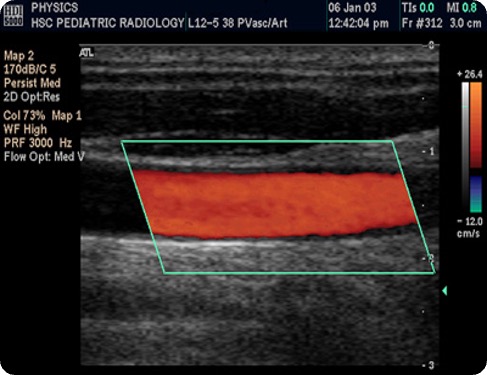

In der Regel wird der Doppler-Modus farbkodiert dargestellt. Dabei entspricht rot meist einem Fluss zum Schallkopf hin und blau einem Fluss vom Schallkopf weg.

Darstellung der A. carotis interna: Der Doppler-Modus (grün umrandet) ist auf den B-Mode „drübergelegt“